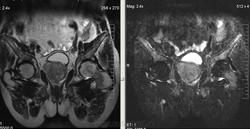

Метастазы рака простаты, кроме измений в позвонках видна сама первичная опухоль и лимфатические узлы (общий и наружный подвздошные слева, ещё один в левой подвздошной ямке).

После добавления томограмм исследования органов малого таза картина стала ещё печальнее...

Да, запустил пациент. До этого были проблемы с мочеиспусканием, рези, болезненность. Лечился самостоятельно от простатита, отмечал временное улучшение.